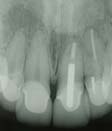

治療例1 前歯4本の審美障害の治療例

前歯4本に審美障害があります。【女性】

4本のセラミッククラウンが装着されています。